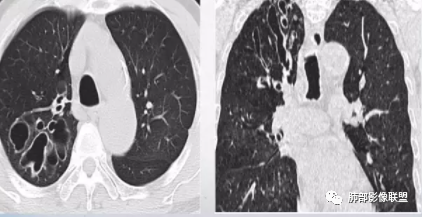

晨读:双肺多发大小不等囊腔影,部分囊有融合,形态不规则,部分壁偏薄,部分囊壁偏厚,囊壁可见结节?血管?右肺上叶及左肺下叶可见条状高密度影,双侧胸膜结节样增厚,临床年轻女性,考虑LAM,鉴别LIP

晨读,青年女性,双肺及胸膜下多发大小不等囊腔,大部分呈薄壁,部分囊壁略厚,边缘毛糙,部分囊腔有融合,双肺内散在条状高密度影,考虑LAM

影像:双肺散在囊性病变,不规则,壁厚,部分见结节

晨读:女,31,间断咳嗽、咳痰9月。卵巢交界性囊腺瘤术后。胸部CT:双肺多发大小不等薄壁囊腔影,部分融合,形态不规则,个别囊壁偏厚。右肺上叶及左肺下叶纤维索条影。左下叶不规则囊腔影,壁不均匀增厚,周围不规则实性成分加GGO,放射性毛刺,胸膜牵拉。考虑:囊腔型Ca?转移?鉴别PLCH,Lam,LIp,BHD,CF,CPAM等,听大咖解析。

胸部CT:两肺多发囊腔,中上肺受累为主,囊腔形态不规则(囊有点丑),分叶状,囊壁厚薄不均,大部分囊壁薄。尚有一些结节影。